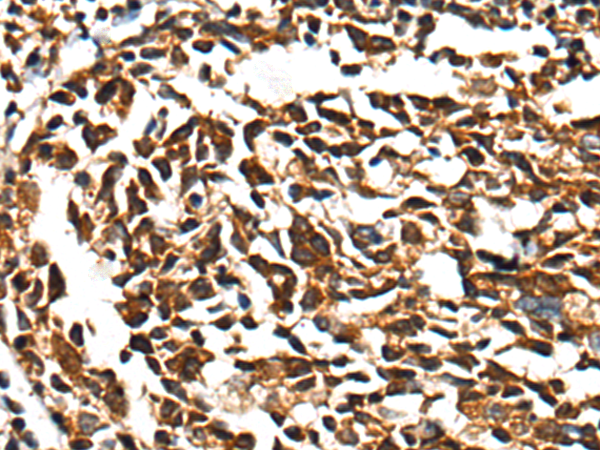

IHC positive control: |

Human lung cancer and human tonsil |

IHC Recommend dilution: |

25-100 |